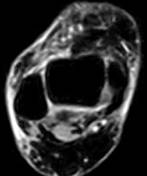

Рис. 4. Левый – полный разрыв задней малоберцово-таранной связки (стрелкой показана часть связки в точке фиксации к малоберцовой кости). Правый – гематома в зоне повреждения (×). |